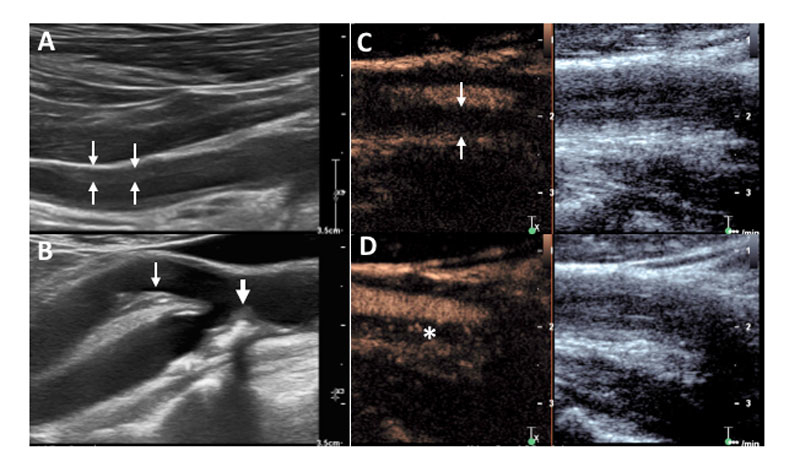

Colour duplex sonography (CDS) assesses the vascular wall anatomy as well as the lumen and it allows the measurement of blood flow. Vasculitis of the temporal arteries shows as homogenous, typically hypoechogenic (dark), circumferential vessel wall thickening. At the temporal arteries, this finding is referred to as the “halo sign”, because of the halo-like appearance around the coloured lumen in cross-sections (fig. 1A) [17]. We recently established the “compression sign”: when applying transducer-imposed pressure on the temporal arteries, a non-vasculitic artery can be compressed and vanishes on the B-mode image (fig. 1B, C). In contrast, an artery with vasculitis-associated wall thickening is not fully compressible and remains visible under compression (fig. 1D, E). The compression sign relies on B-mode ultrasound only, making it less examiner- and device-dependent. Nonetheless, it still has a sensitivity and specificity comparable to the halo sign [18]. As with temporal arteries, vasculitis of large arteries (e.g., axillary, carotid) also presents as circumferential homogenous hypoechogenic wall thickening (fig. 2A). Stenosis, or even occlusion, can be present. In lower limb arteries an echo-lucent ribbon within the thickened wall can be another sign of vasculitis [7]. In contrast to vasculitis, advanced arteriosclerosis shows more heterogeneous, eccentric, irregular plaques, typically with acoustic shadowing mostly in the carotid and femoral and popliteal arteries (fig. 2B).

Figure 2 Large vessel findings in colour duplex sonography (CDS) and contrast-enhanced ultrasound. (A) Vasculitis of an axillary artery with homogeneous, typically circumferential, hypoechogenic vascular wall thickening in CDS. (B) Arteriosclerosis in the carotid arteries showing irregularly shaped, eccentric hypo- and hyperechogenic (with acoustic shadowing) plaques in the internal (thick arrow) and external (thin arrow) carotid artery. (C, D) Common carotid artery in another patient with large-vessel vasculitis showing strong hypervascularisation of the vessel wall. (C) Enhanced vessel lumen without contrast bubbles within the thickened vessel wall (arrows) immediately after destroying all bubbles by a so called “flush”. (D) Reappearance of the contrast bubbles within the arterial wall (asterisk) indicates hyperaemia/vascularisation.

Contrast-enhanced ultrasound (CEUS) complements and enhances standard CDS, particularly in the setting of inflammatory vascular diseases [20]. Ultrasound contrast agents contain gas-filled microbubbles. After intravenous injection, the microbubbles distribute in the vascular system down to the capillary perfusion level. By using contrast specific ultrasound imaging modalities, their physical properties make them readily detectable in the microcirculation and allow demonstration of hypervascularisation and hyperaemia in the inflamed vessel wall (fig. 2C, D) [21].